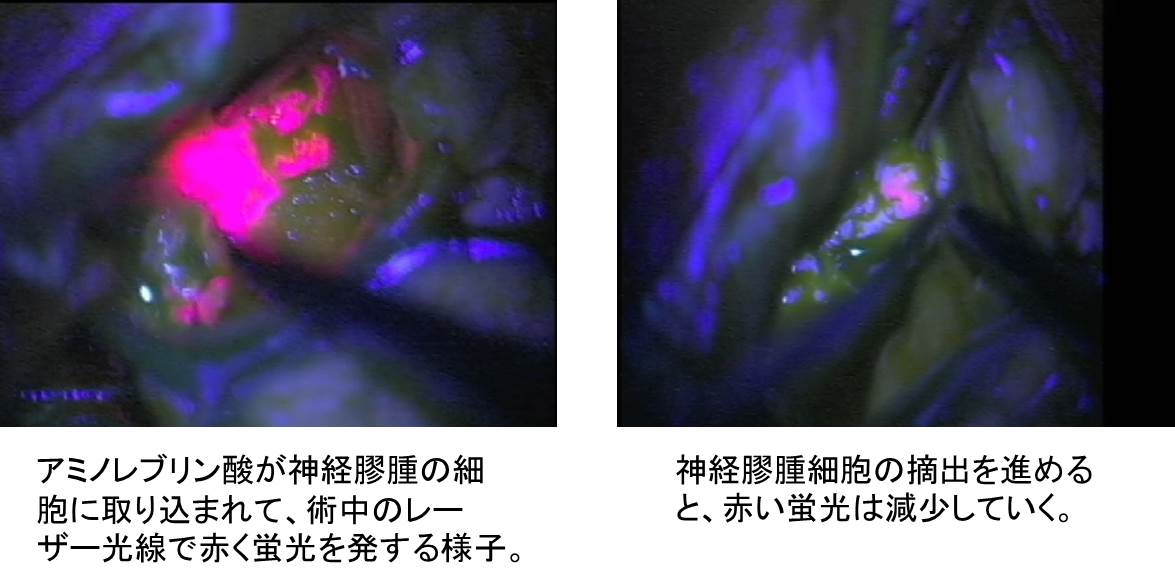

次世代型の手術室で 脳腫瘍の術後生存率が劇的に向上 日常生活への